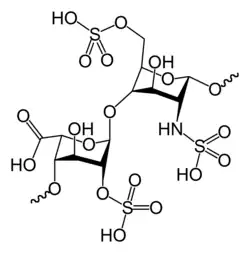

| Medicação | Heparina de baixo peso molecular, varfarina, anticoagulantes orais diretos[2][4] |

A anticoagulação é essencial para prevenir novos trombos, mas não age diretamente em coágulos existente. Deve ser feito uma avaliação entre o risco de trombose e o risco de hemorragia (custo-benefício) antes de determinar a dose e duração da anticoagulação. Três meses geralmente é o padrão, mas em pessoas com doenças nas válvulas cardíacas ou histórico de AVC pode durar anos e necessitar frequentes regulações da dose. Os anticoagulantes mais usados são as heparinas, as cumarinas (como acenocumarol) e a warfarina.[13]